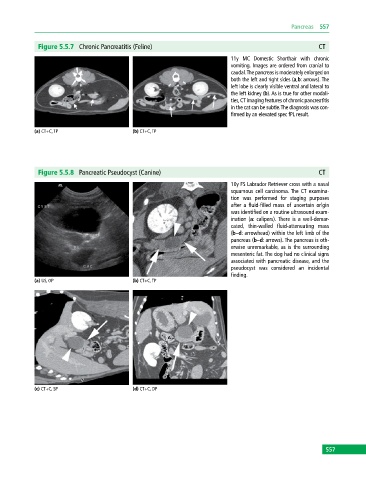

Figure 5.5.7 Chronic Pancreatitis (Feline) CT

11y MC Domestic Shorthair with chronic

vomiting. Images are ordered from cranial to

caudal. The pancreas is moderately enlarged on

both the left and right sides (a,b: arrows). The

left lobe is clearly visible ventral and lateral to

the left kidney (b). As is true for other modali-

ties, CT imaging features of chronic pancreatitis

in the cat can be subtle. The diagnosis was con-

firmed by an elevated spec fPL result.

(a) CT+C, TP (b) CT+C, TP

Figure 5.5.8 Pancreatic Pseudocyst (Canine) CT

10y FS Labrador Retriever cross with a nasal

squamous cell carcinoma. The CT examina-

tion was performed for staging purposes

after a fluid‐filled mass of uncertain origin

was identified on a routine ultrasound exam-

ination (a: calipers). There is a well‐demar-

cated, thin‐walled fluid‐attenuating mass

(b–d: arrowhead) within the left limb of the

pancreas (b–d: arrows). The pancreas is oth-

erwise unremarkable, as is the surrounding

mesenteric fat. The dog had no clinical signs

associated with pancreatic disease, and the

pseudocyst was considered an incidental

finding.

(a) US, OP (b) CT+C, TP

(c) CT+C, SP (d) CT+C, DP